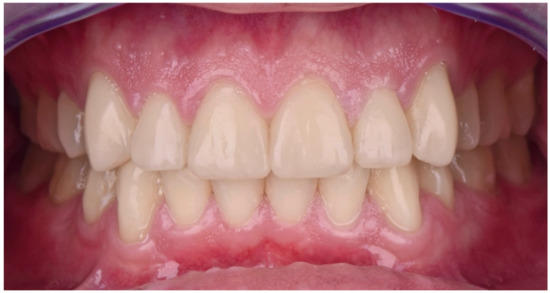

2. Clinical Report

2.2. Restorative Phase